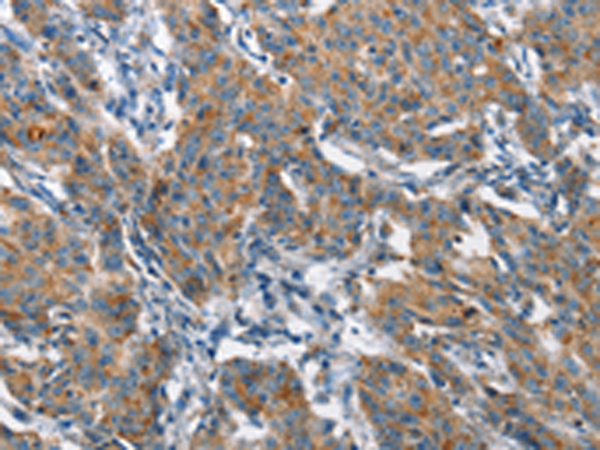

分类: 科研抗体货号: P08161别名: LB1; TMAP; se20-10应用: IHC反应种属: Human